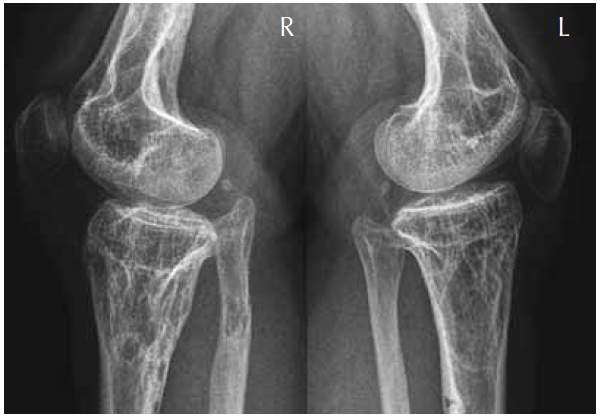

Lateral radiograph of the inferior femora and the super tibiae showed abundant calcification intermixed with areas of osteolytic lesions. Note multiple lucent lesions with bony islands and linear sclerotic changes, which extend from the epiphyses to involve the shafts (Fig. 2).

Fig. 2. Lateral radiograph of the inferior femora and the super tibiae showed abundant calcification intermixed with areas of osteolytic lesions. Note multiple lucent lesions with bony islands and linear sclerotic changes, which extend from the epiphyses to involve the shafts